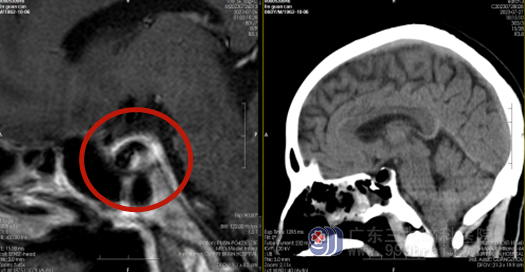

影像检查:

术前MR